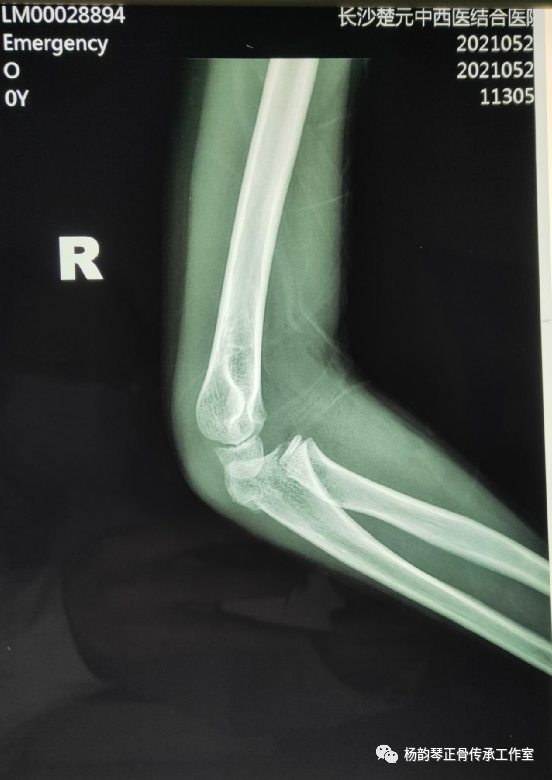

辅助检查:X线片:右尺骨近端骨折,右桡骨头脱位。

孟氏骨折特别容易漏诊的就是桡骨头脱位,此患者从侧位片上看可以看到桡骨近端纵轴线没有通过肱骨小头中心,提示肱桡关节匹配不良,桡骨头脱位。除非直接暴力导致尺骨骨折,一般单纯尺骨骨折比较少见,临床上看到尺骨骨折就必须密切关注肱桡关节匹配情况,桡骨头脱位后可能自动还纳,若此时忽略对桡骨头的固定,可能发生再脱位。所以即使X线片仅见骨折而无脱位,一般最好也按孟氏骨折来处理,避免漏诊。

入院后予以手法复位,小夹板外固定,拍片复查示骨折对位对线良好,桡骨头脱位已纠正。具体复位手法:术者一手拇指先摸清桡骨头位置,将拇指置于肘前方,然后另一手握前臂置于前臂旋后位,再极度屈肘,拇指卡于肱骨与桡骨之间形成杠杆,通过极度屈肘促使桡骨头复位。用锐角托板固定于患肢屈肘60°(邻肢夹角法)前臂旋后位。